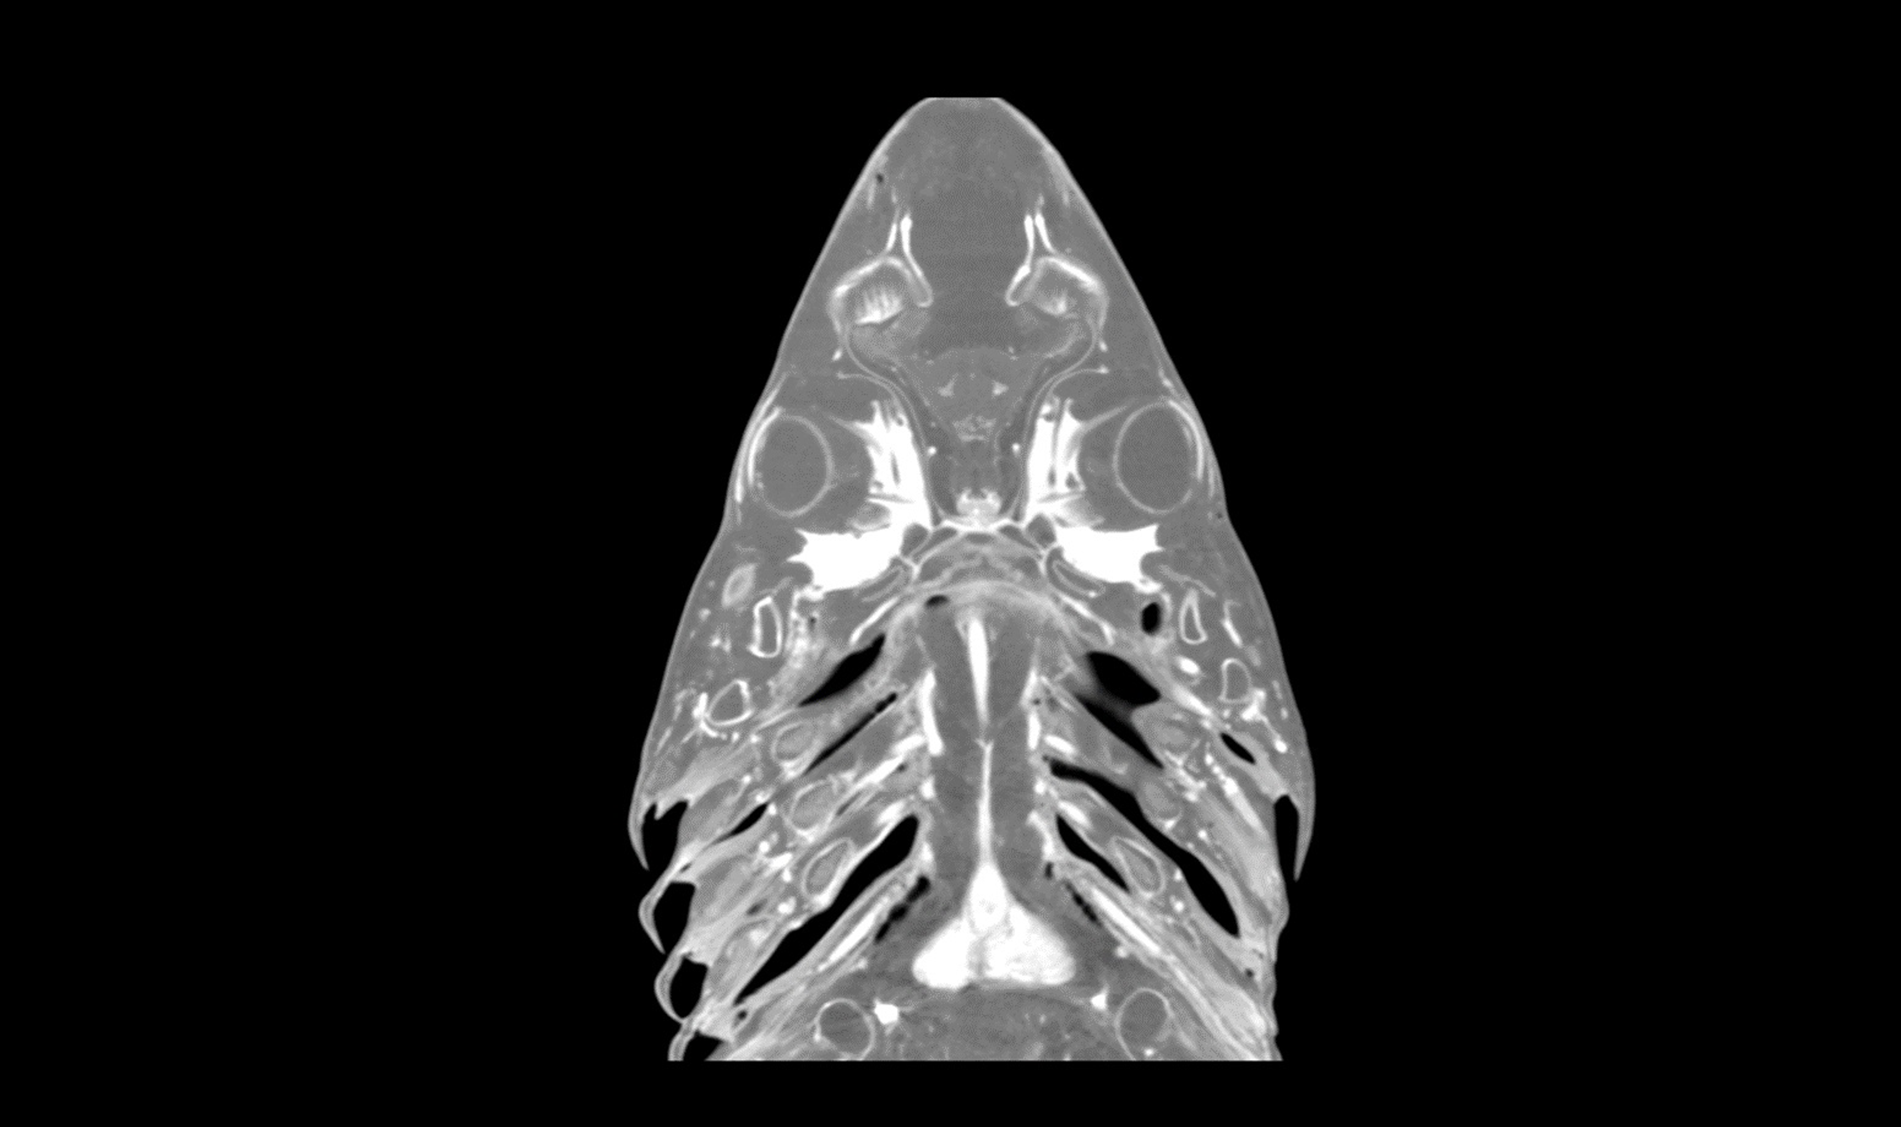

HDVI and HRCT

CONTRAST RESOLUTION

Enhanced soft tissue imaging capability.

ISOTROPIC VOXEL

True Multi Planar Reconstruction (MPR) imaging.

MULTIMODALITY

Computed Tomography, Fluoroscopy and Digital Radiography all in one.

Advancing Veterinary Care

Our scanners represent a point of reference for the veterinary profession, allowing targeted interventions and effective treatments for four-legged friends.